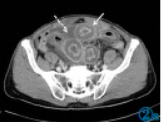

患者于检查当日(8月30日)夜间出现双侧足背、小腿伸面多发性皮下淤点,大小形态不等,颜色为深红色,压之不褪色。诊断为AAP。临床予以“甲强龙40mgivgttqd×3d”抗炎、抗过敏以及补液对症等治疗,患者腹痛明显好转,下肢皮疹明显消退,复查CT显示,肠壁水肿好转,肠腔扩张管径约为3.4cm,系膜渗出改变好转,腹盆腔积液吸收(图3)。

图3AAP好转CT表现。腹部CT平扫显示小肠壁水肿好转,肠腔扩张(白色箭头所指),盆腔积液吸收。